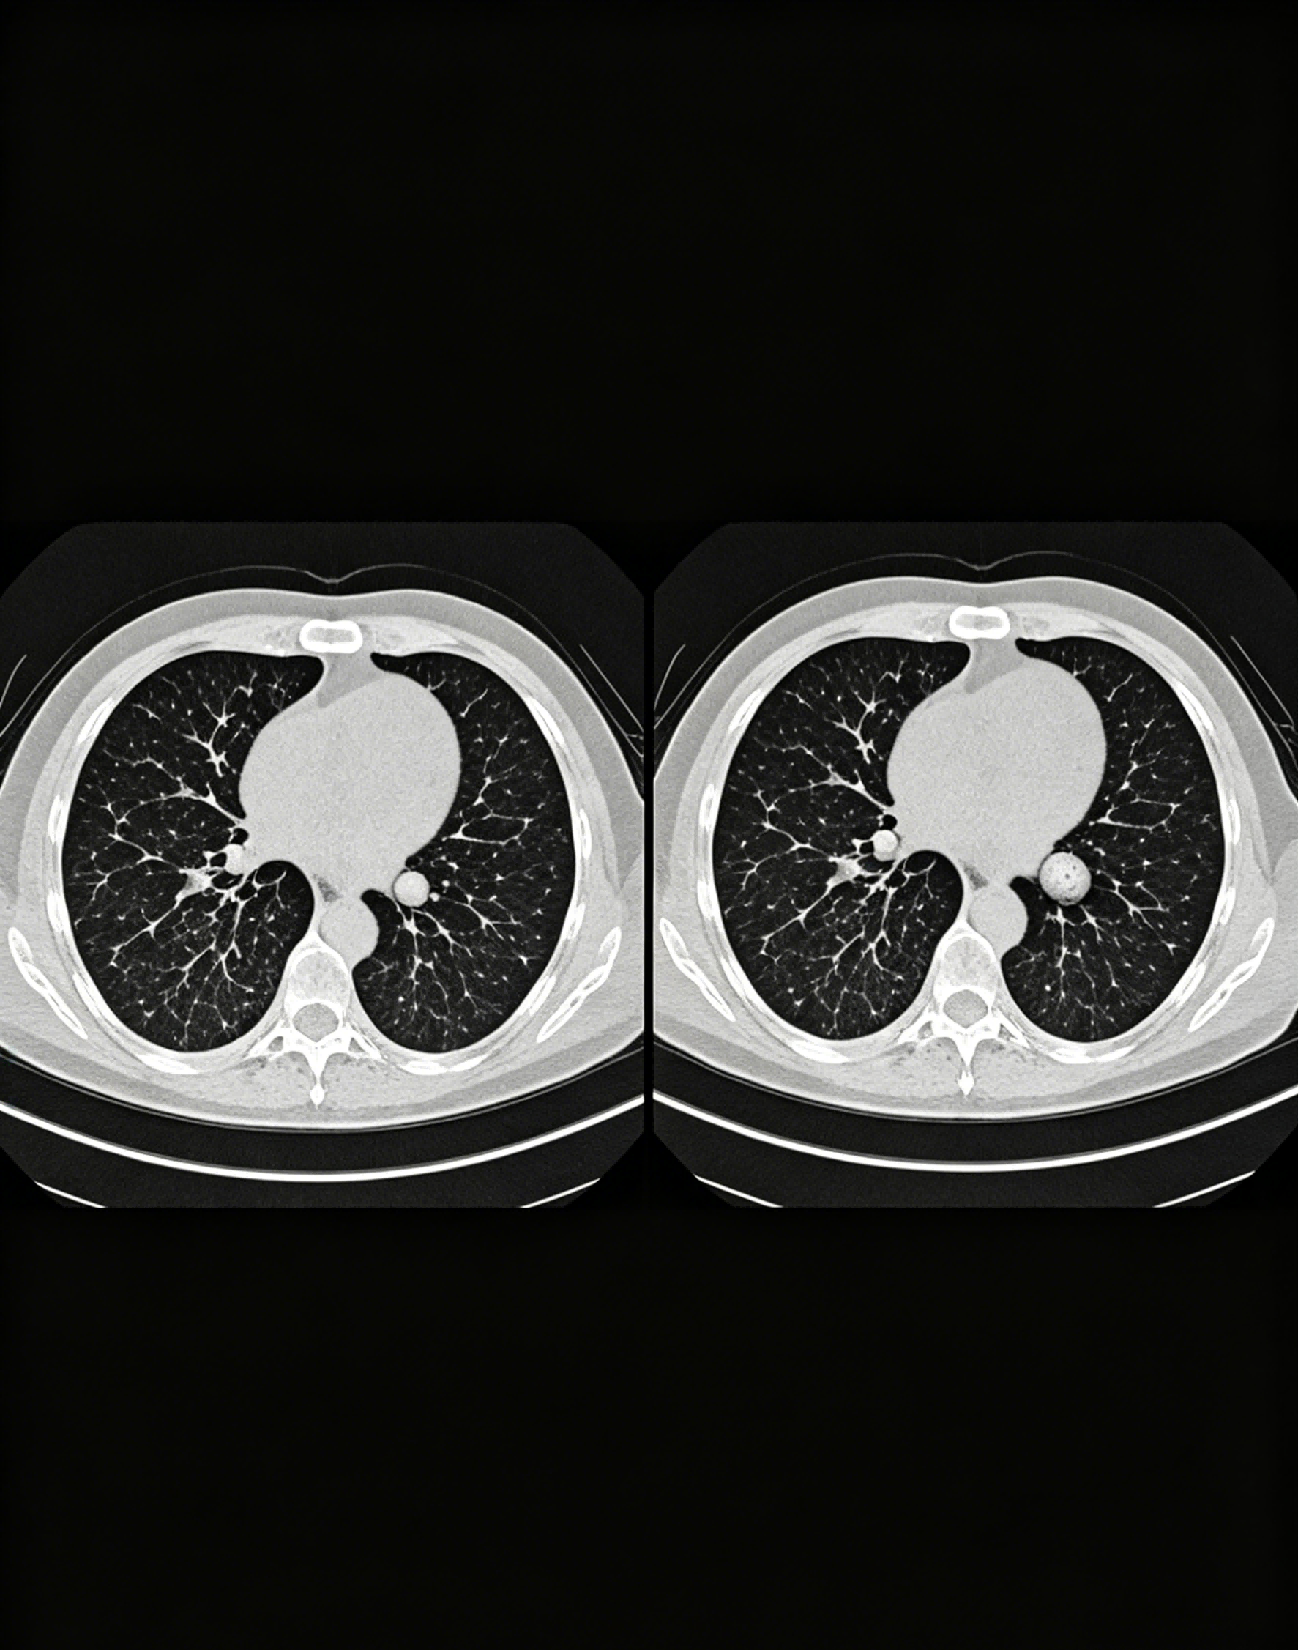

肺部结节变小通常是好转的迹象,尤其是炎性结节、良性结节,结节缩小或消失,多提示病因得到控制、病情逐渐恢复,但需结合结节性质、检查结果综合判断,不能仅凭结节变小就完全判定好转,仍需定期复查确认。肺部结节是肺部出现的圆形或类圆形占位性病变,分为良性和恶性,不同性质的结节,变化意义不同。​

但需注意,少数恶性结节初期可能因炎症包裹、治疗暂时控制等出现短暂变小,后续可能再次增大,因此不能仅凭一次结节变小就放松警惕。尤其是磨玻璃结节、混合磨玻璃结节,即使变小,也需定期复查,观察结节形态、密度的变化。此外,结节变小的速度、幅度也需关注,若结节快速缩小,多为良性;若缩小缓慢或伴随形态异常,仍需进一步检查排除恶性可能。​